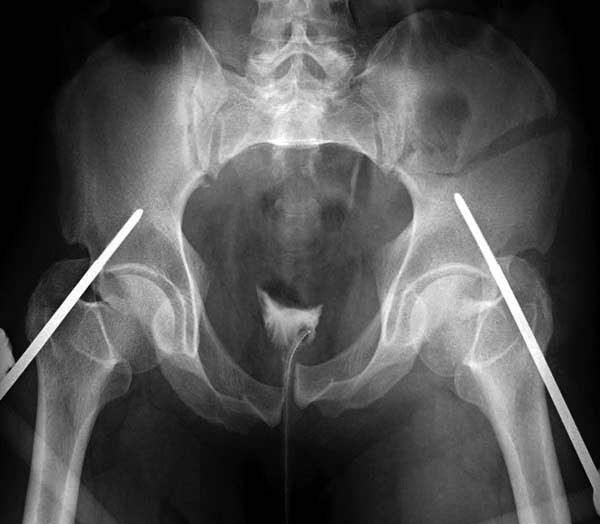

Здесь представлен случай 38 летнего больного (падение с высоты 9 метров) с нарушением тазового кольца. При поступлении для стабилизации передне-нижний аппарат наружной фиксации и на 6й день, вчера, операция из двух доступов.

Наружные фиксаторы создают не только стабильность костей таза, а также в экстренных случаях помогают уменьшить обьем таза в профилактике кровотечения!

Представлены снимки техники проведения стержней. Через место прикрепления прямой мышцы в Inferior Iliac Spine в направления вырезки создается жесткость. Weber clamp изнутри таза для репозиции, и фиксация после репозиции перелома крыла подвздошной кости. Наружный аппарат удален, нагрузка предполагается через два месяца.